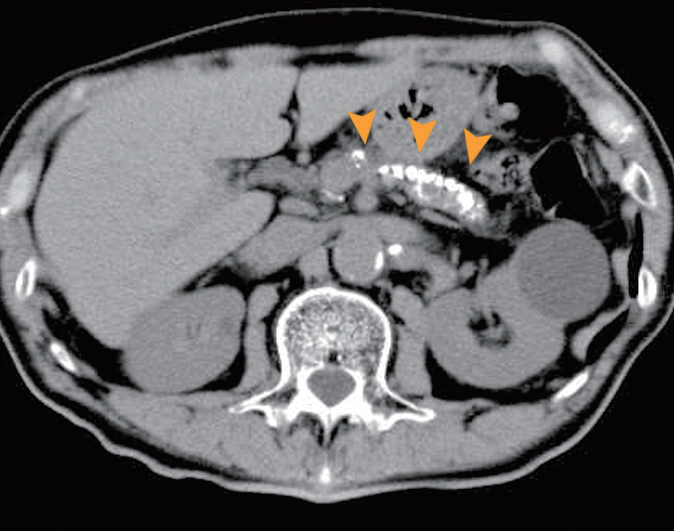

- 영상 검사 : 초음파, CT 스캔, MRI 등을 통해 췌장의 상태를 확인하고 담석이나 염증의 정도를 평가합니다.